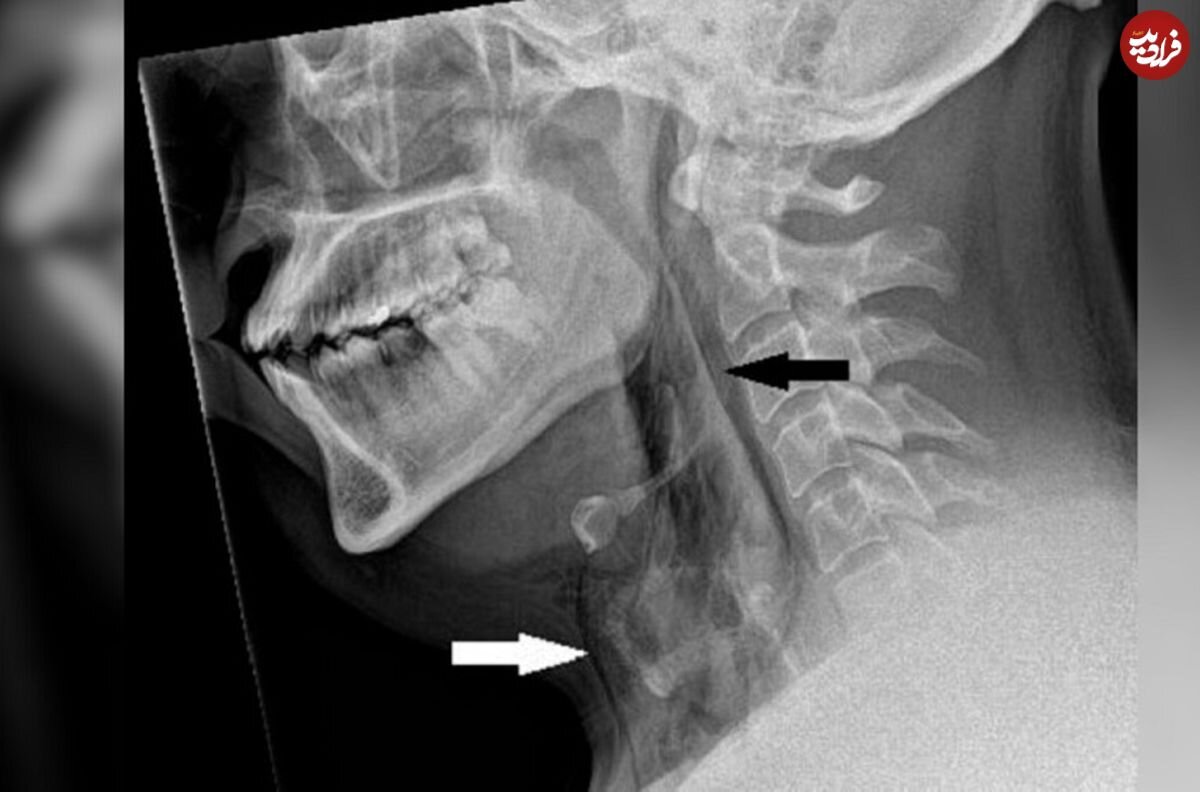

عکسبرداری با اشعه ایکس از گردن نشان داد مرد مبتلا به آمفیزم زیرپوستی است، بیماریای که در آن، هوا زیر عمیقترین لایههای بافت زیر پوست گیر میکند. توموگرافی کامپیوتری (سیتیاسکن) نشان داد پارگی بین استخوانهای سوم و چهارم یا مهرههای گردن او رخ داده است. هوا نیز در فضای قفسهسینه بین ریههای او جمع شده بود. پزشکان به این نتیجه رسیدند که پارگی ناشی از افزایش سریع فشار در نای هنگام عطسه با بینی فشرده و دهان بسته است.